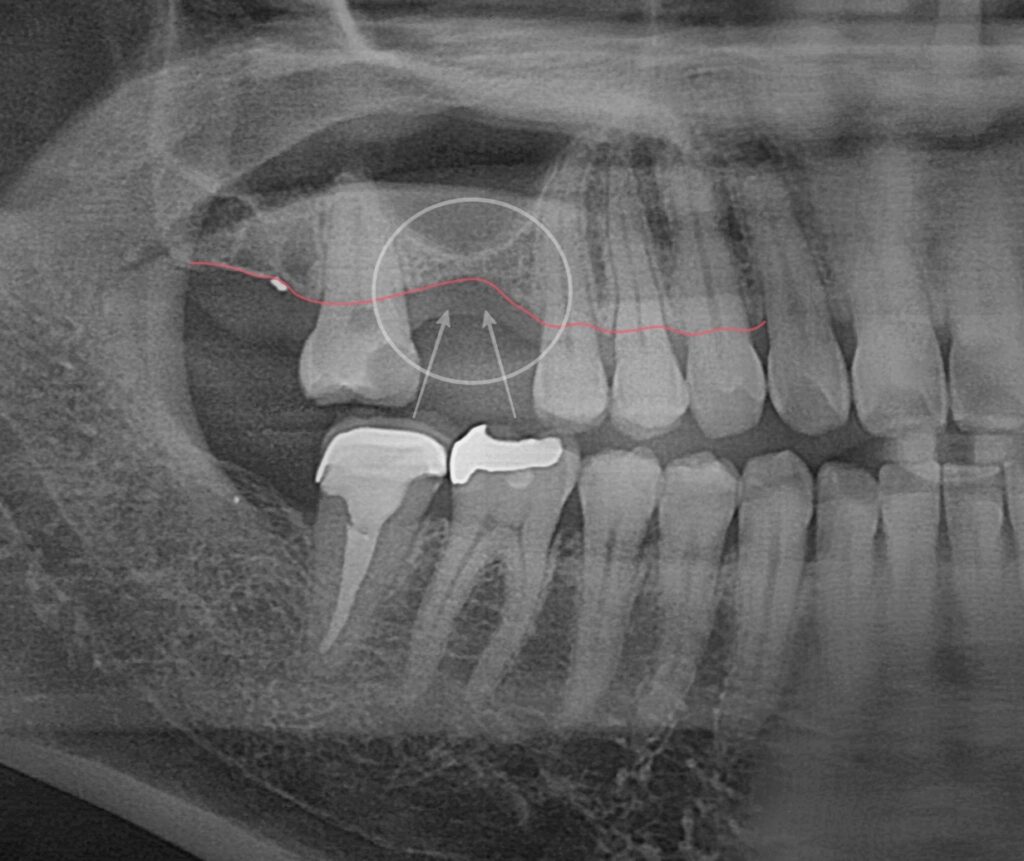

3. 골흡수와 상악동의 관계

단순 기능적인 회복을 생각하면

양옆의 치아를 지대치로 삼는

브릿지 보철이 있습니다.

다만 이 또한 치조골에는 자극을 주지 못해

골흡수의 진행을 막기 어렵습니다.

반면 임플란트는 잇몸 골조직에

직접 압력을 전달 할 수 있는 방식이므로

이를 해결할 수 있는 치료가 됩니다.

그러나 위쪽 어금니에 식립하는 경우

조심스럽게 접근해야 됩니다.

그 이유는 상악동의 존재입니다.

이에 민락 치과 에서 설명해 드리면

얼굴의 양쪽 광대 쪽에 존재하는

부비동의 일종으로써

우리가 숨을 쉬고 소리를 내는 데에

큰 역할을 하는 주요 조직입니다.

그러나 치조골의 두께가 얇아짐과 동시에

이곳이 아래쪽으로 내려오게 됩니다.

이를 상악동의 함기화라고 말하며

임플란트를 식립하는 데 있어

큰 위험 요소가 될 수 있습니다.

얇은 막으로 구성되어 있어

쉽게 찢어지고 천공으로 이어지는

부작용을 일으킬 수 있기 때문입니다.

사진을 보면 상악동 거상술이

잘 마무리된 것이 확인됩니다.

충분한 공간이 확보되어

상악동에는 큰 영향이 없이

픽스처가 자리 잡고 있습니다.